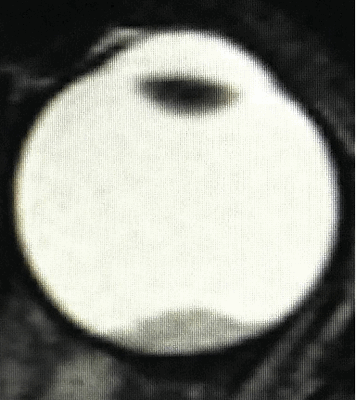

Ретинобластома характеризуется быстрым ростом и вследствие недостаточного кровоснабжения некротизируется. В очагах некроза откладываются соли кальция, образуя характерные для больших опухолей кальцификаты. Классически различают два вида макроскопического роста опухоли — эндофитный, при котором опухоль растет в направлении центра глаза, разрушая внутренние слои сетчатки и стекловидное тело, и экзофитный, или стелящийся, при котором опухоль инфильтрирует преимущественно наружные слои сетчатки, распространяясь в сторону субретинального пространства.

Большие опухоли с экзофитным ростом могут вызвать отслоение сетчатки с последующим накоплением субретинального транссудата. Оба вида роста опухоли не имеют значимого прогностического значения.

Ретинобластома может иметь эндофитный тип роста в направлении центра глазного яблока: при этом происходит разрушение слоев сетчатки и стекловидного тела. При другом варианте роста - экзофитном, ретинобластома инфильтрирует сетчатку, распространяясь в субретинальное пространство. Экзофитные опухоли могут вызывать отслойку сетчатки и скопление транссудата в субретинальном пространстве. В редких случаях (1-2%) встречается инфильтративная форма ретинобластомы, которая ведет к диффузному истончению сетчатки, накоплению экссудата в передних отделах глаза, развитию передних спаек и псевдогипопиона.

- D - рассеянные опухоли с крупными опухолевыми массами, разнокалиберными отсевами в стекловидном теле и/или субретинальном пространстве в более чем 3 мм от новообразования с субретинальной жидкостью более 6 мм от образования, включая полную отслойку сетчатки (рис. 3 и 4).

![Визуализация ретинобластомы с помощью МРТ. Размеры образования соответствуют клинической группе D]()

Рис. 3. Визуализация ретинобластомы с помощью МРТ. Размеры образования соответствуют клинической группе D